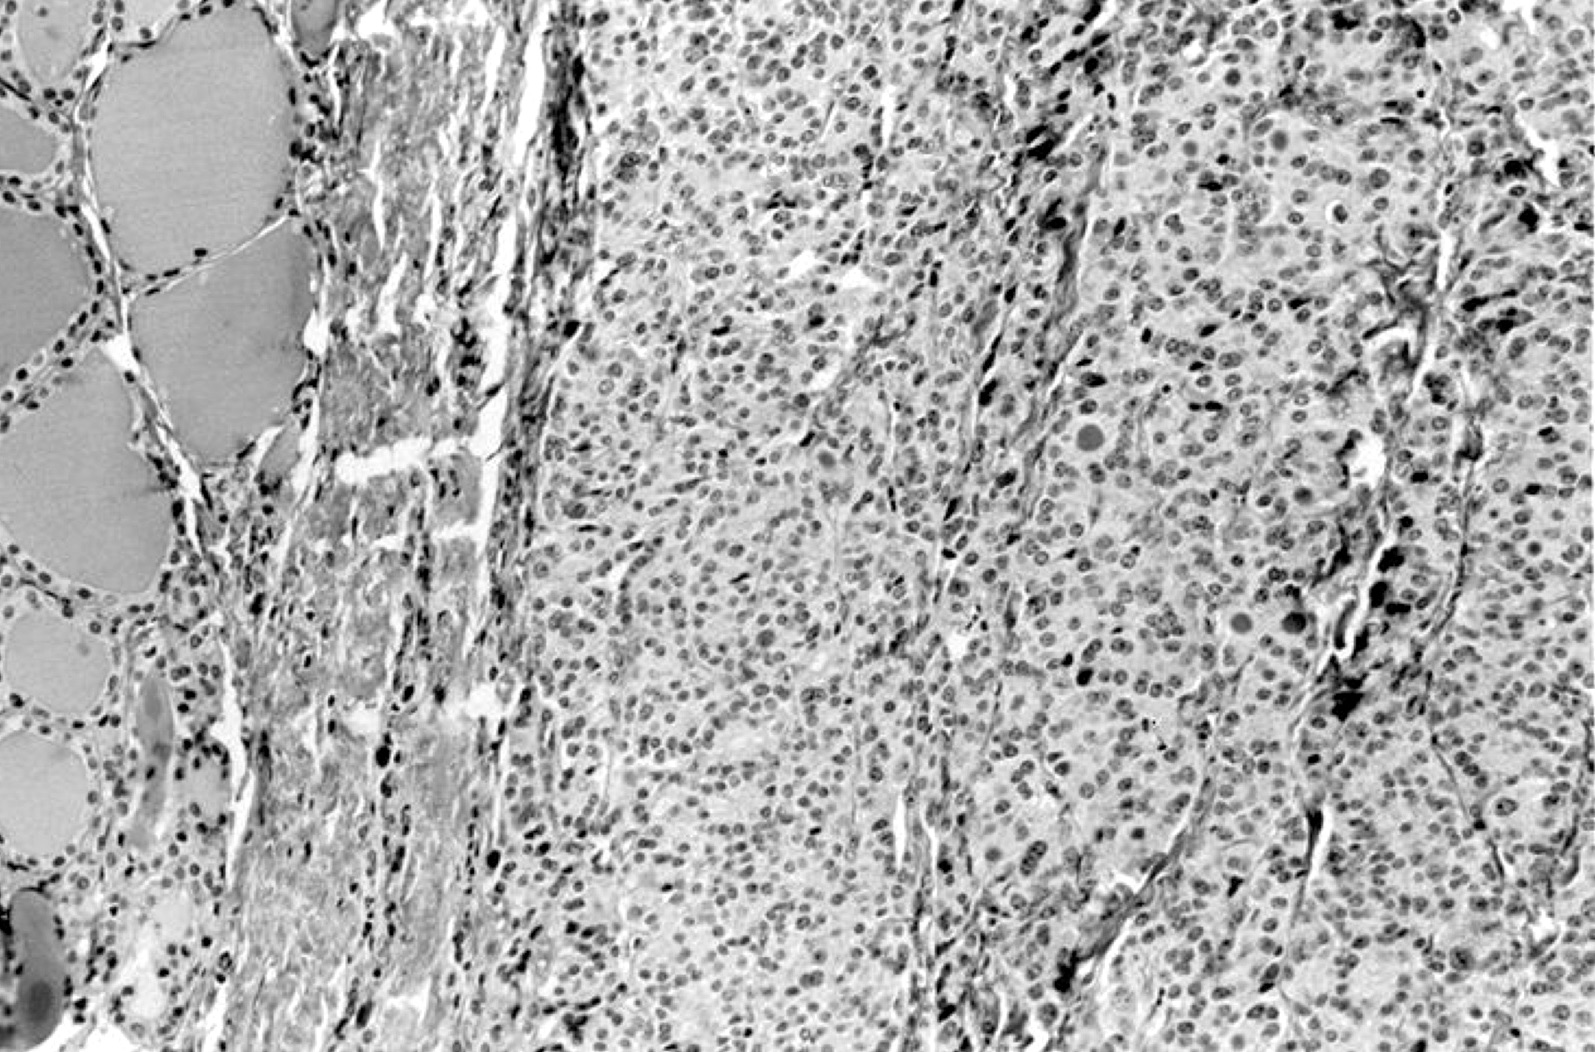

Microscopic (histologic) images

Contributed by Shipra Agarwal, M.D., Andrey Bychkov, M.D., Ph.D., Mark R. Wick, M.D., Asmaa Gaber Abdou, M.D. and AFIP

Atypical adenomas:

Not invasion:

- Encapsulated; thin or moderately thick capsule

- No capsular or vascular invasion after thorough sampling (at least 10 blocks)

- Minimally invasive follicular thyroid carcinoma:

- Thick capsule

- Vascular or capsular invasion

- May show increased mitotic activity; may have foci of necrosis